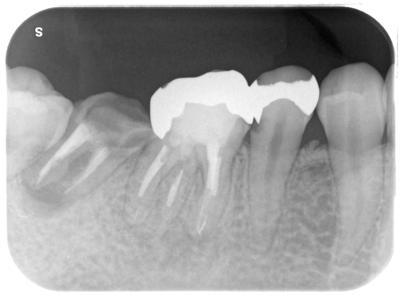

7┓部へのITI-BLXインプラントによる治療。

この部位へのインプラント治療には様々な治療設計、議論はあると思うが、他の歯牙の状況、全顎的矯正治療を行っている事、その他患者さんの要望からこのような治療計画となった。

2次オペ後8┓のMTM予定。無論、65┓その他の補綴治療も。

7┓は虫歯が深く、大きく膿が溜まっており保存不可能。

6┓も根尖に影=膿が溜まっている、しかも前医によるファイル破折が起きているが、何の説明もなかったとのこと。

虫歯も深い。

6┓は根管治療行ったが、マイクロスコープ下でも破折ファイル片の除去はできなかった。無理して除去続行し、歯をダメにしては元も子もないので、徹底的に根管洗浄、一部MTAによる根管充填行った結果、根尖病巣は縮小、消失した。

深い虫歯には歯周外科処置を行っている。